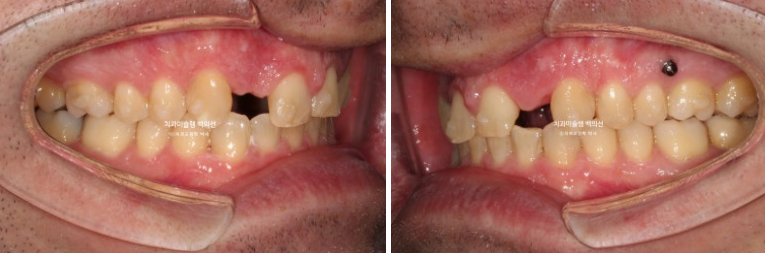

오늘은 부원장님 인비절라인 케이스를 보면서 앞니 2개가 선천적으로 없는 경우 (결손치) 인비절라인 교정 후 임플란트까지 치료 진행과정에 대해 보여드리겠습니다.

24년 1월 교정치료를 위해 내원한 외국인 환자분입니다.

23.01

위 앞니 4개중 2개가 없습니다. 앞니가 크게 벌어져 있고 아래 앞니가 위로 솟아 위 입천장 잇몸을 칠 정도의 심한 과개교합이 있습니다.

만약 이렇게 선천적 결손치아와 돌출입이 혼재한다면 결손치아를 발치한 셈 치고 벌어진 공간을 모으며 돌출을 해소하는 방향으로 치료를 하기도 합니다.

하지만 환자분은 전형적인 caucasian의 안모를 보입니다.

즉 입술이 얇고 콧대가 높고 턱끝이 튀어나와 앞니가 뒤로 더 들어가면 큰일날 상입니다.

이런 경우라면 공간을 한쪽으로 몰아 결손치 자리에 임플란트를 하는 것이 좋습니다.

앞니 자리로 밀려온 송곳니를 원위치로 보내어 결손된 앞니자리에 임플란트 2개를 하기로 했습니다.